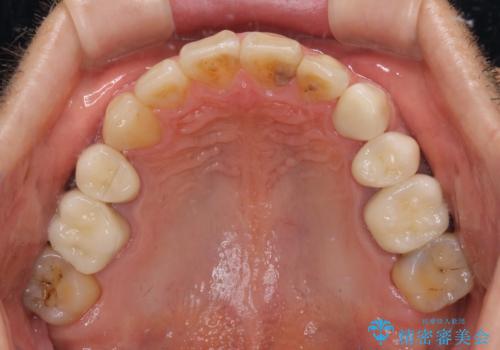

- むし歯による奥歯の痛みを気にして来院された患者様です。

神経にまでむし歯の及んでいる歯や、既に根管治療がされている歯に痛みがあったため、まずは根管治療を行うこととしました。

その後、以前行った抜歯矯正の後戻りをインビザライン・ライトにより改善し、むし歯や銀歯はオールセラミッククラウンにて補綴治療することとしました。

痛みは速やかに引き、銀歯や黒く変色したむし歯がセラミッククラウンで自然な色合いに仕上がり、患者様には大変満足していただきました。